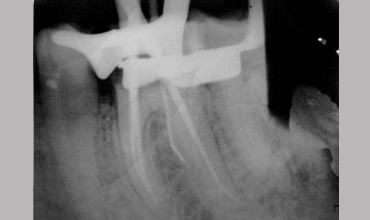

Management Of Radix Entomolaris In Mandibular First Molar